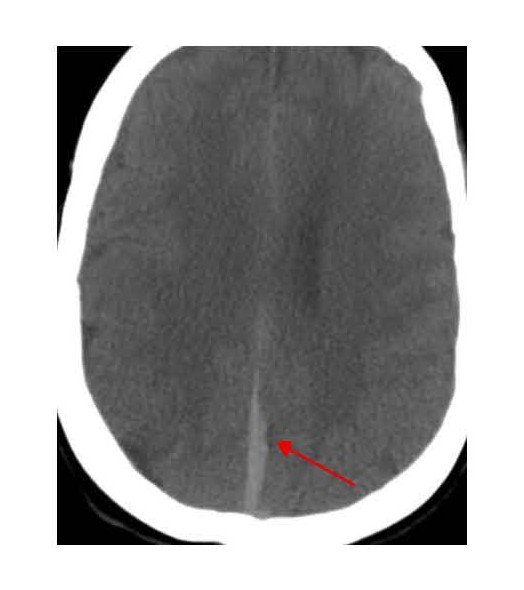

The patient became hypoxic and tachypneic, and showed pink frothy sputum and declining mental status, therefore intubation and mechanical ventilation were required. After blood and urine cultures were obtained, broad-spectrum antibiotics were started because of concerns regarding aspiration pneumonia and sepsis. CT angiography of the head yielded findings concerning for right vertebral artery dissection. She was transferred to our institution for neurosurgery, interventional neurology management, and neurocritical care. On arrival, she received another CT head without contrast, which showed extensive SAH centered at the basal cisterns and surrounding the brainstem, with subdural hematomas along the tentorium and posterior falx, and intraventricular hemorrhage within the occipital horns and the third and fourth ventricles (Figures 3 and 4).

Figure 3. Head CT showing blood in the third ventricle.

Figure 4. Head CT showing subdural blood along the falx cerebri.